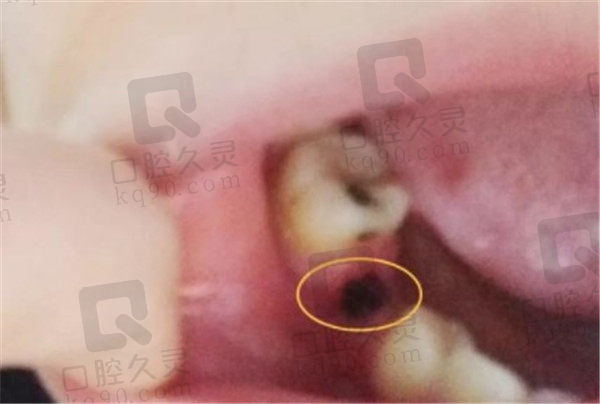

术前诉求:这位女士因为牙齿没有保护好,因为龋坏后槽牙有一颗牙齿脱落,想种植一颗比较自然真实的牙齿

刘院长根据顾客的诉求,已经口腔状况,选择了瑞典诺贝尔种植体+全瓷冠的方式给顾客进行牙齿种植

术后反馈:种植体植入手术全程都是在无菌手术室里进行的,进入手术室经过了消毒,牙齿种植手术全程我被用绿布遮盖,植牙手术期间不太压抑,除了打麻药的时候疼了下,其他时候都很舒适。时间也很短,大概30分钟之后我就拥有了一颗真牙,从外观看诊的很难发现和旁边的牙有什么区别